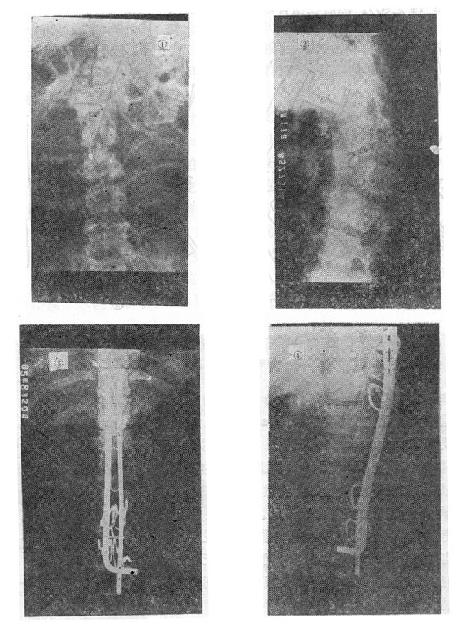

(五)切片状骨折的治疗 因为这种骨折伴有整个韧带的完全撕裂,且常合并截瘫,用Harrington撑开棍治疗后方间隙反而会明显增宽。应选用强度较好的Luque或Dick装置为好,不仅能获得满意的复位(图73-16①~③),而且固定牢固,术后即可随意翻动病人,术后1-2即可让病人起床坐轮椅活动,有利于截瘫病人的康复与护理。

切片骨折的治疗

图73-16 切片骨折的治疗